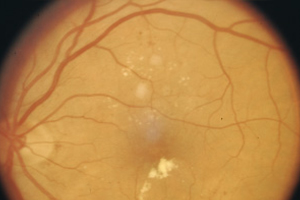

Bei beiden Formen der diabetischen Retinopathie kann zusätzlich die Stelle des schärfsten Sehens (Makula) ebenfalls mit betroffen sein. Dies führt zu einer stärkeren Verminderung der Sehschärfe (diabetische Makulopathie).

Proliferative Retinopathie – Augenärztliche Gemeinschaftspraxis | Dr. Heuring, Dr. Jung & Kollegen

Feine Fettablagerungen in der Makula

Ausgeprägte Fettablagerungen in der Makula